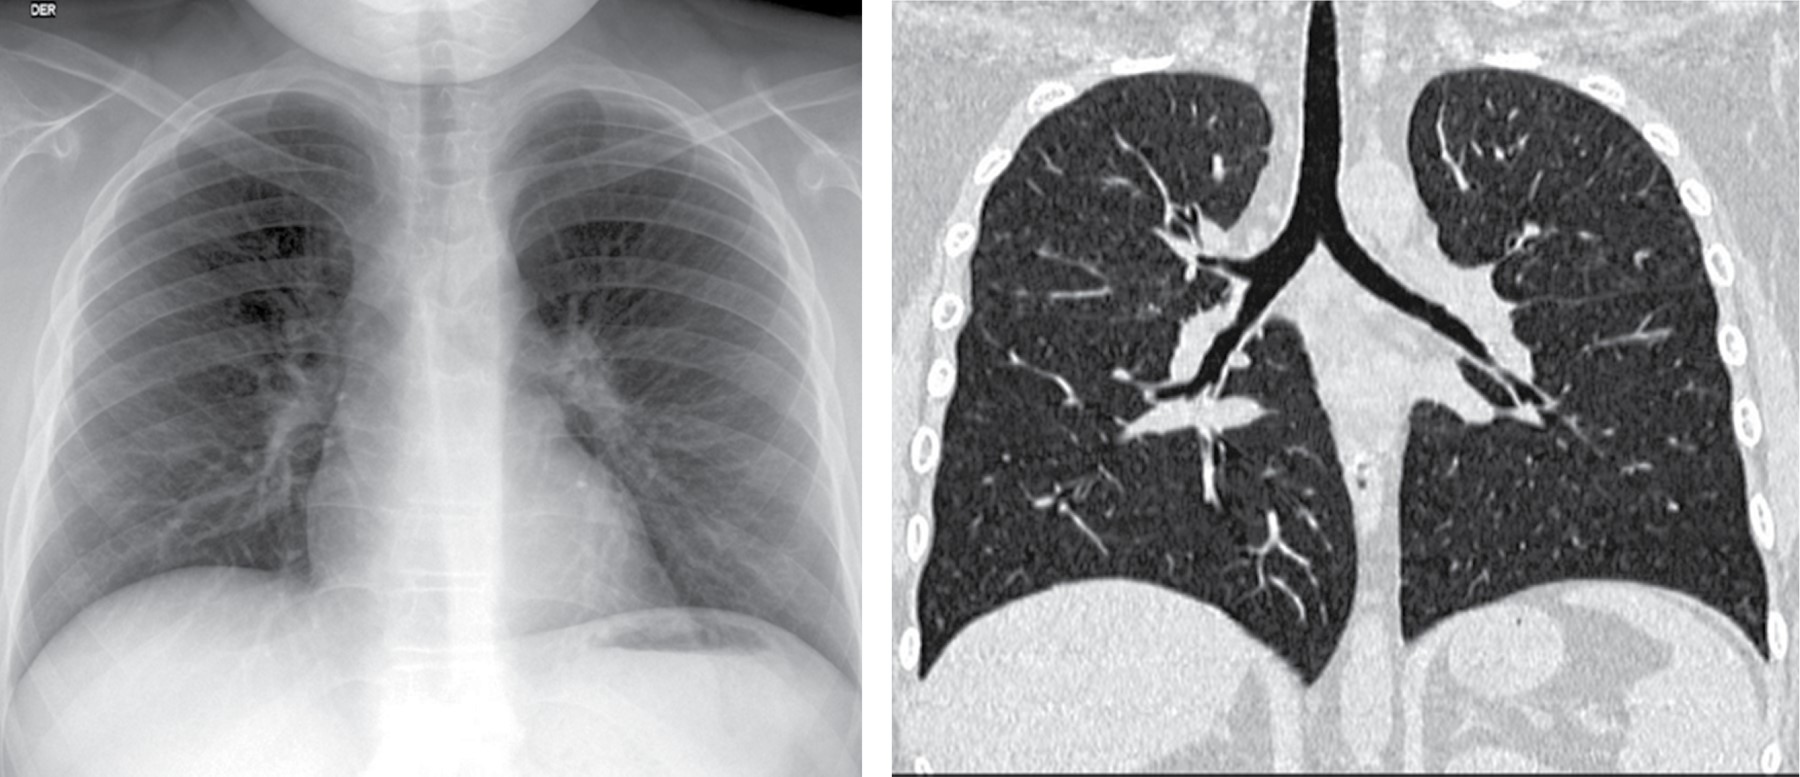

La radiografía de tórax mostró ensanchamiento mediastinal y un patrón intersticial grueso a expensas de intersticio perilobulillar bilateral y difuso, casi simétrico con algunas imágenes nodulares también difusas (Figura 9). En la TACAR contrastada se corrobora el patrón intersticial perilobulillar con nódulos difusos con discreto predominio subpleural así como zonas de atelectasia bilateral subpleurales y en lóbulo medio (Figura 10). En la ventana mediastinal se demuestran crecimientos ganglionares paratraqueales de predominio derecho, en ventana aortopulmonar y axilar bilateral. A nivel abdominal lesiones nodulares hipodensas múltiples hepatoesplénicas sugestivas de granulomas (Figura 11). Se realizó biopsia de piel en cara, la cual mostró dermatitis granulomatosa epitelioide no caseificante, compatible con sarcoidosis (Figura 12).

Las pruebas de función respiratoria iniciales mostraron un patrón sugestivo de restricción moderada, sin respuesta significativa al broncodilatador. La broncoscopia mostró traqueobronquitis leve y gastritis antral, baciloscopias en serie de tres y prueba de PPD reportadas negativas. La biopsia de piel reveló granulomas desnudos compatibles con sarcoidosis. Para la uveítis recibió prednisona ocular al 1%. Fue tratado por otro servicio con tres pulsos de metilprednisolona a 30 mg/kg/día, prednisona oral a 0.7 mg/kg/día y micofenolato de mofetilo 42 mg/kg/día (1 g VO cada 12 horas) sin respuesta. Cambiamos a prednisona en dosis de 1 mg/kg/día y metotrexato a 15 mg/m2/semana, hubo respuesta favorable desde las cuatro primeras semanas de tratamiento; la enfermedad está inactiva, pero el paciente cursa con tos, disnea, cianosis distal, y baja saturación de O2, todo lo anterior traduce un daño pulmonar permanente (Figuras 13 y 14).

La sintomatología puede ser aguda, subaguda o crónica, cursando asintomáticos 30% de los casos. En ambos pacientes la sintomatología fue subaguda. Durante los siguientes dos a cinco años desde el inicio de los síntomas, más de 60% de los pacientes experimentan una resolución completa de la enfermedad, pero en el restante 30% puede seguir un curso crónico, que en algunos casos termina en fibrosis pulmonar con síntomas respiratorios permanentes como ocurrió en el caso 2 con daño pulmonar permanente.5,9,18